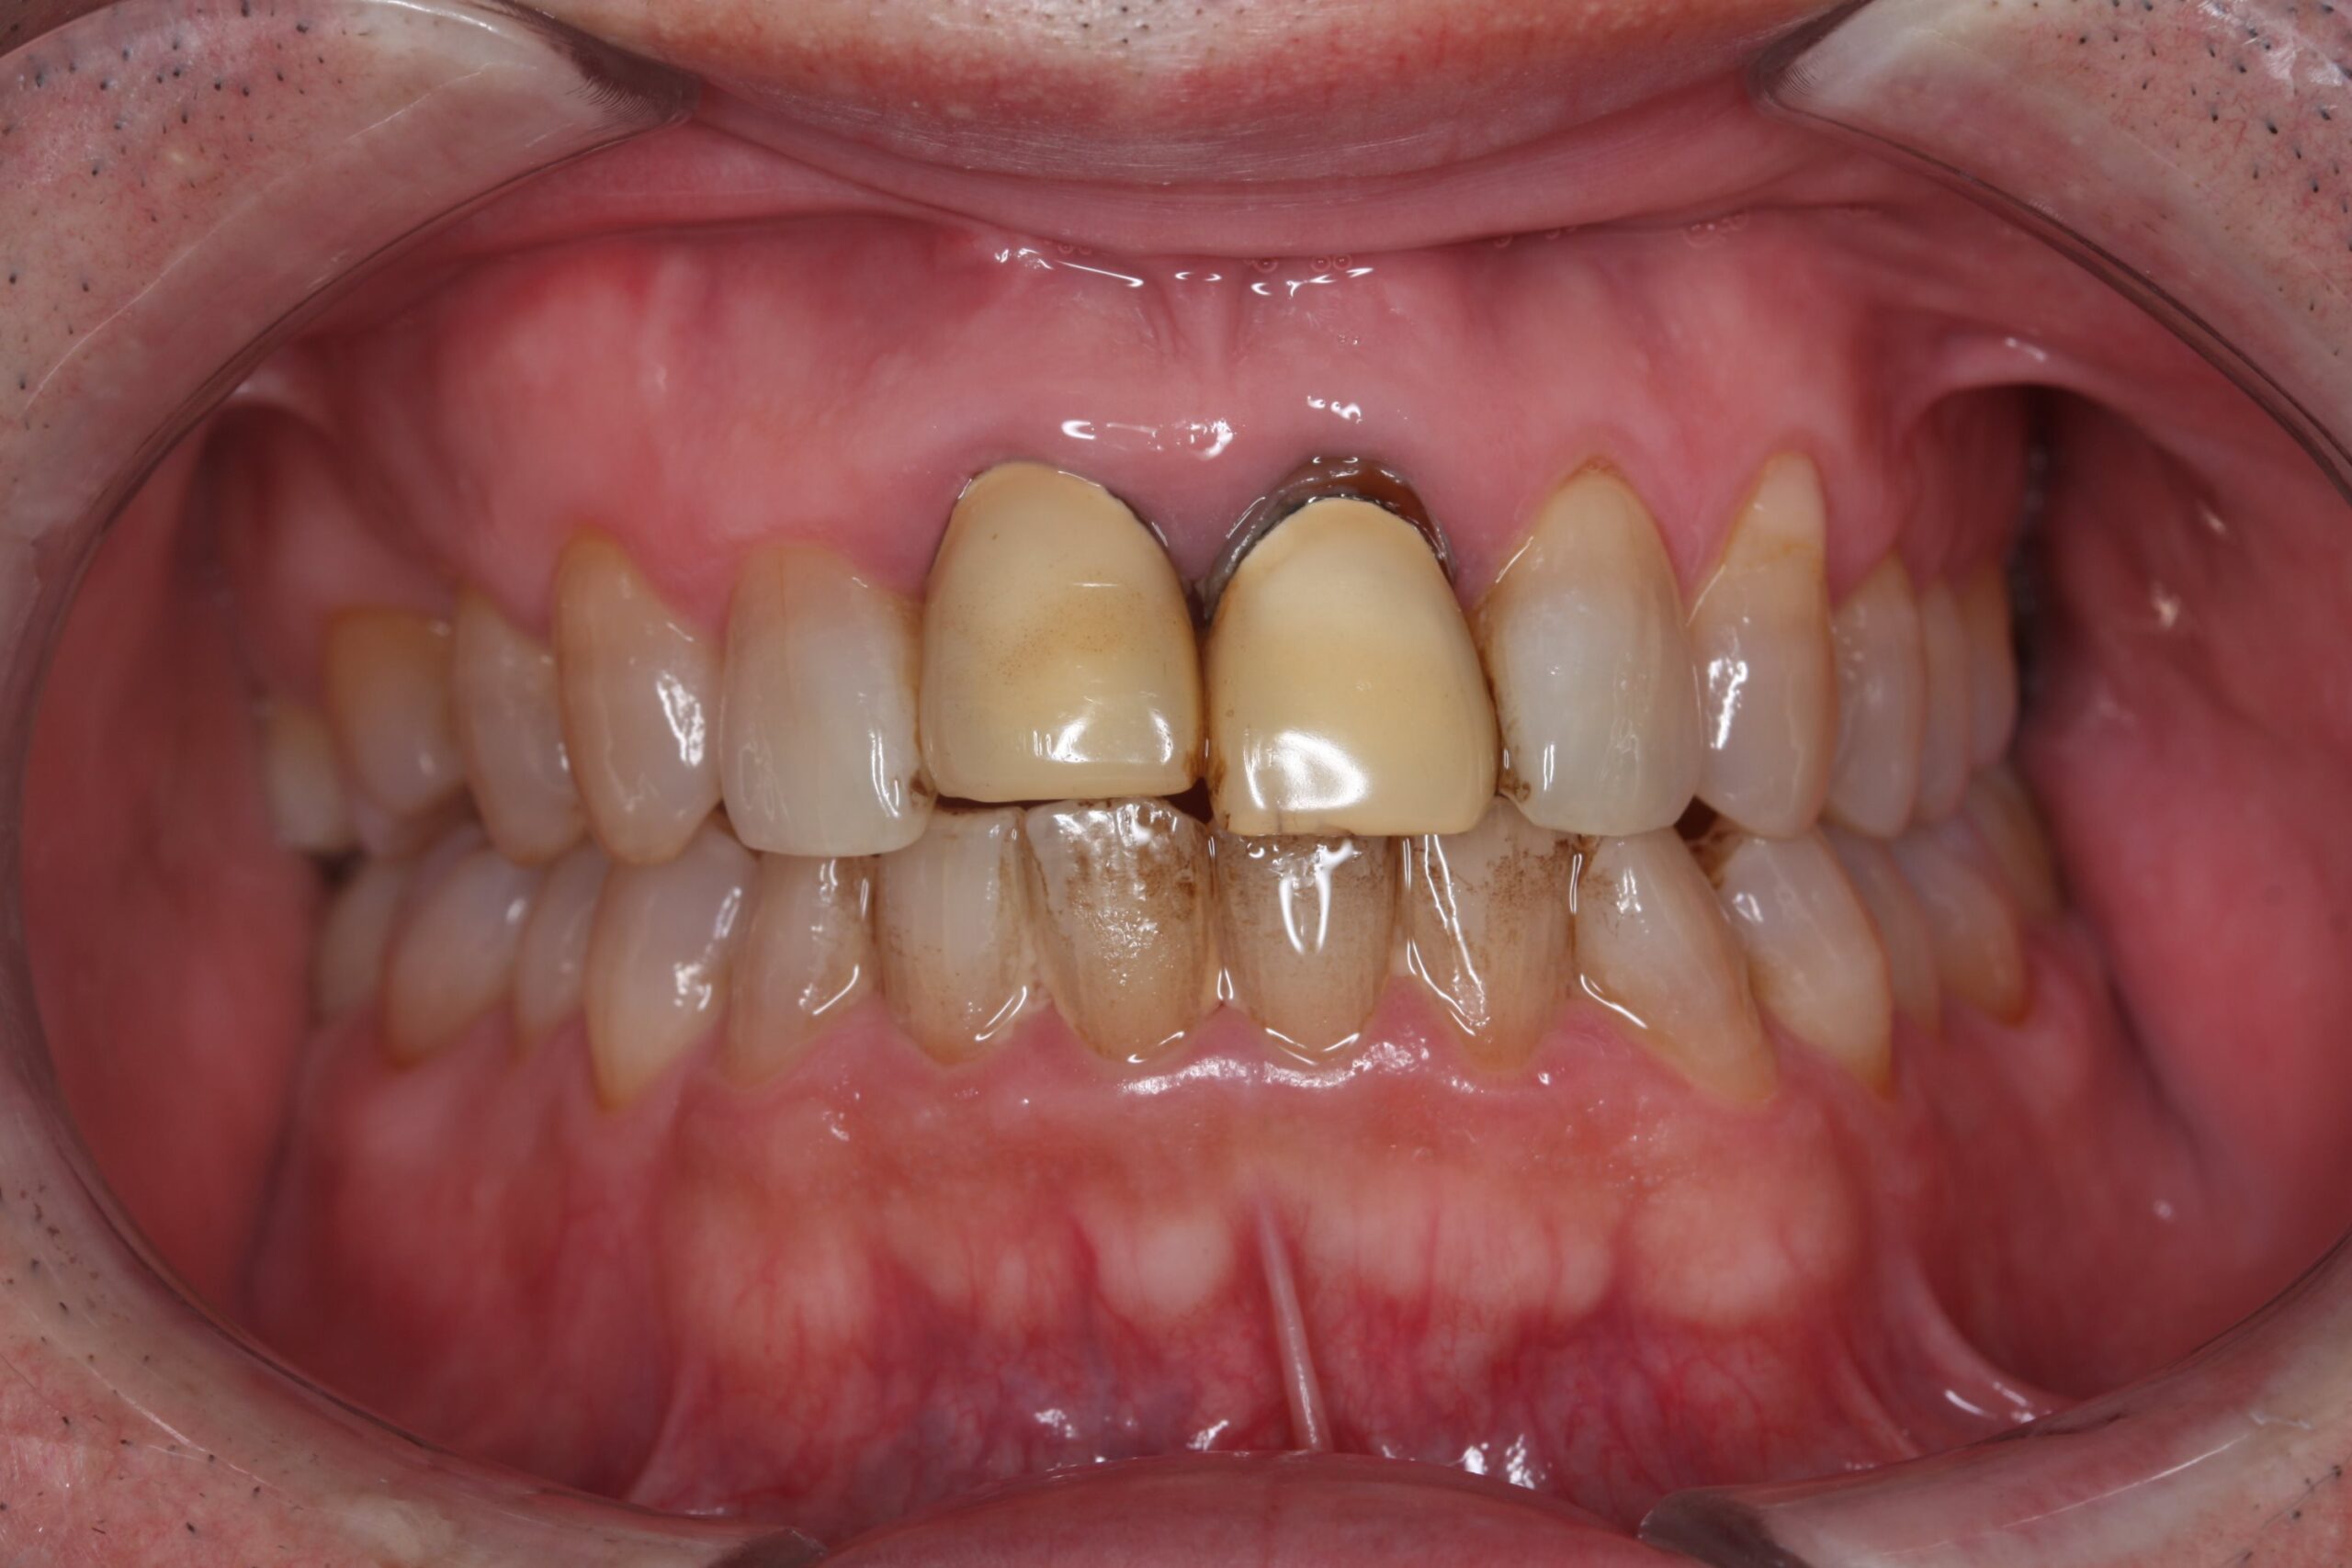

治療前

40年ほど前に治療した上顎前歯。以前、他院にて、治療を提案されていたとのこと。

当院での治療を希望された。 -